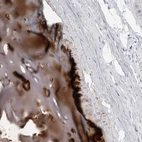

Immunohistochemical staining of human soft tissues shows strong cytoplasmic positivity in chondrocytes.